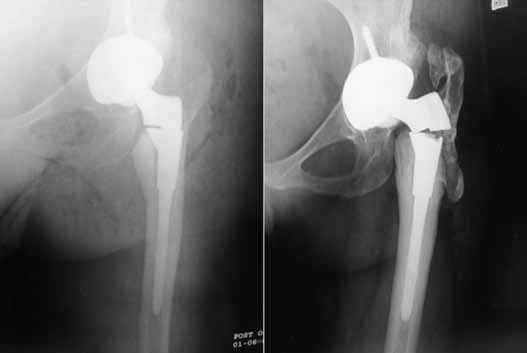

Перипротезный перелом

Это - нарушение целостности бедренной кости в зоне ножки при нестабильном и стабильном протезе, возникающее интраоперационно или в любой момент после операции (через несколько дней, месяцев или лет). Переломы чаще происходят по причине сниженной плотности костных тканей, но могут быть следствием некомпетентно произведенной разработки костного канала перед установкой искусственного сочленения, неверно выбранного способа фиксации. Терапия в зависимости от вида и тяжести повреждения заключается в использовании одного из методов остеосинтеза. Ножку, если на то заменяют на более подходящую по конфигурации.

Разрушение импланта происходит очень редко.